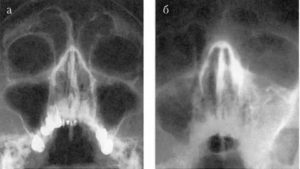

Одним из главных диагностических методов является рентгенография. В некоторых случаях может быть назначена компьютерная томография или МРТ. Выявление затемнения в левом верхнечелюстном синусе позволяет с высокой степенью уверенности диагностировать левосторонний гайморит.